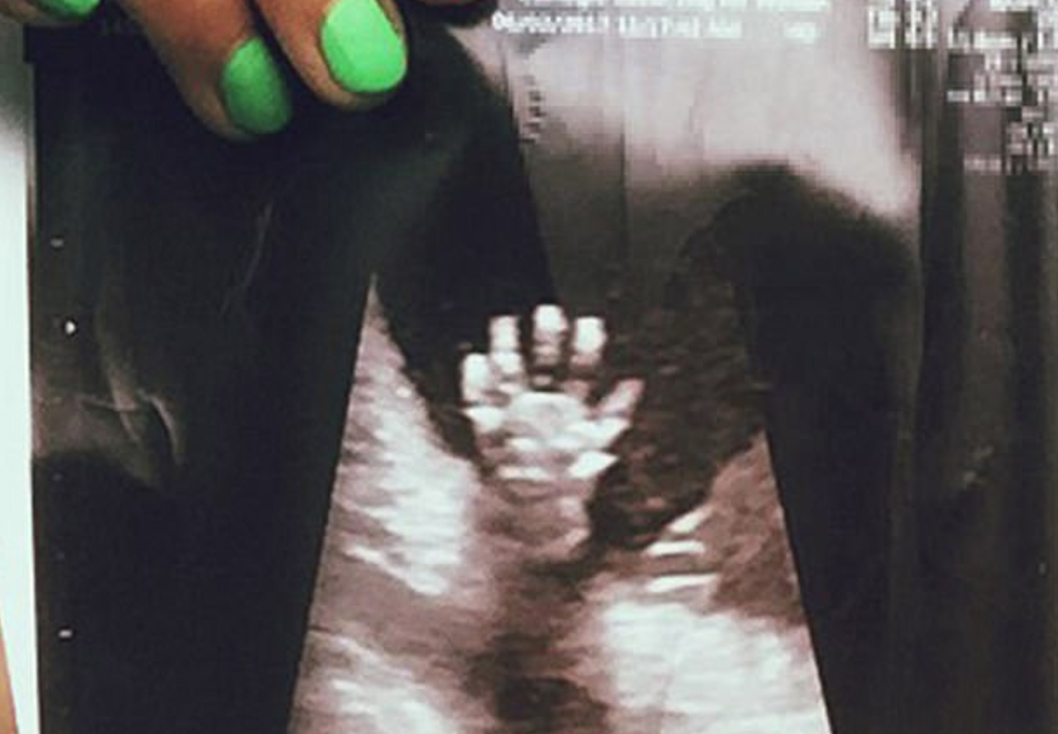

The amazing moment an unborn baby appears to 'hi-five' its parents

Expectant parents were left astounded after their unborn baby appeared to give them a high five from the womb. Â

But it was at their 20-week scan that the pair got their biggest surprise yet - when they saw their baby daughter's hand reaching up to give them a high five, from the womb.